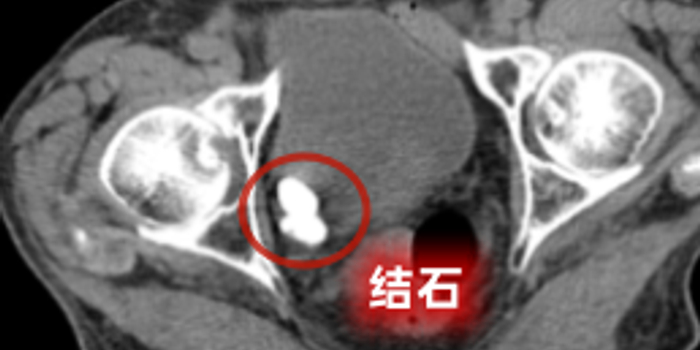

入院完善检查后,泌尿外科发现张爷爷病情复杂,不仅确诊膀胱多发结石、前列腺增生,还合并癫痫、脑血管狭窄、颈动脉狭窄等多种基础疾病,加之高龄,手术麻醉风险、术中术后并发症风险均显著高于普通患者。

在多学科紧密配合下,手术团队精准定位膀胱内多发结石,利用钬激光将结石逐一击碎并顺利取出,同时精准处理前列腺增生问题,全程操作平稳顺利。术后,在医护团队精心护理与个体化康复指导下,张爷爷尿频、血尿、夜尿频繁等困扰已久的症状得到明显改善,饮食、睡眠及排尿情况逐步恢复正常,对治疗效果十分满意。